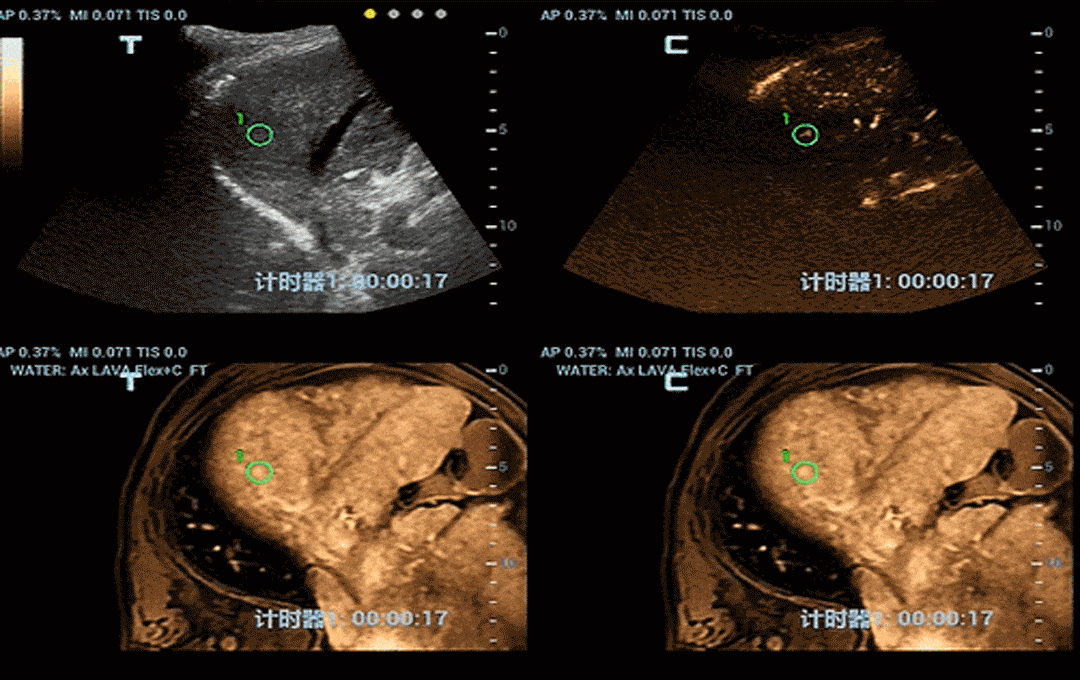

Besides Respiration Compensation, the quad mode has also been highly validated and welcomed by clinicians. It provides separate fusion imaging of CT/MRI with tissue and contrast enhanced ultrasound images, making it easy to visualize lesions on different types of images. This real-time and comprehensive multiple modality displaying renders better diagnostic confidence.

pc68-s8

Fusion with CEUS renders more confidence on pathology diagnosis